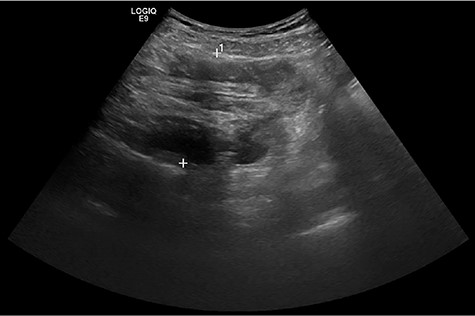

A 51-year-old female patient presented to the emergency department with abdominal pain that started and increased significantly within 1 day. The abdominal pain was described as crampy, appearing first in the periumbilical region with migration to the right lower quadrant. In addition, the patient experienced nausea, but no vomiting and had diarrhea twice that day without blood admixture. The patient’s past medical and family history were unremarkable. In physical examination, the abdomen was non-distended and soft but with rebound tenderness, especially in the right lower and middle quadrant. The rectum was empty and there was no indicator of intestinal hemorrhage. Laboratory tests showed a white blood cell count of 14.5 × 109/L and a C-reactive protein level of 7.0 mg/L. All other studies were within normal limits. An abdominal ultrasound showed a ‘pseudokidney’ sign in the lower abdomen (Fig. 1). Additionally, a computerized tomography (CT) scan of the abdomen and pelvis was performed and revealed an intussusception involving ~20 cm of the ascending and transverse colon (Fig. 2).

Abdominal ultrasound showed a ‘pseudokidney’ sign on the longitudinal view of the lower abdomen.